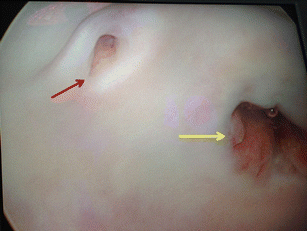

Dueñas-Garcia, O.F., Hall, C.D. Vaginal ectopic ureter simulating preterm premature rupture of membranes. Int Urogynecol J 27, 1773–1774 (2016). https://doi.org/10.1007/s00192-016-3067-8

- Ectopic ureter

- Preterm rupture of membranes

- Urinary incontinence